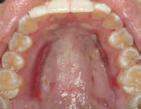

Figura 1. Fotografia inicial, se observa un fenotipo delgado festoneado, estrecha banda de encía queratinizada en zona anteroinferior con sobremordida, apiñamiento y retroinclinación en el maxilar anterior inferior.

En los pacientes con tratamientos de ortodoncia que presentan fenotipos gingivales delgados, pueden estar limitados los movimientos dentales para la corrección de discrepancias esqueletales y malposición dental. Si estas discrepancias y malposiciones dentales, no son bien planeadas por el ortodoncista, puede favorecer a la aparición de recesiones y deformidades mucogingivales.1,2

Paciente femenino de 13 años de edad, acude con sus padres a la clíni ca de periodoncia de la Universidad Popular Autónoma del Estado de Puebla para revisión dental. Al reali zar la exploración clínica, en su aná lisis gingival, la paciente presenta un fenotipo gingival delgado, con estre cha banda de encía queratinizada en el maxilar anteroinferior, edema y eri tema en zona marginal y papilar, acu mulación de biofilm dental en zonas interproximales y marginales, retroin clinación y apiñamiento anteroinfe rior, con una notoria sobremordida y paladar profundo. Posteriormente al realizar periodontograma y aná lisis radiográfico se diagnostica a la paciente con una gingivitis inducida por biofilm dental y según la nueva clasificación del World Workshop del 2017 presenta deformidad mucogin gival alrededor de los dientes por la estrecha banda de encía queratiniza da (Figura 1).